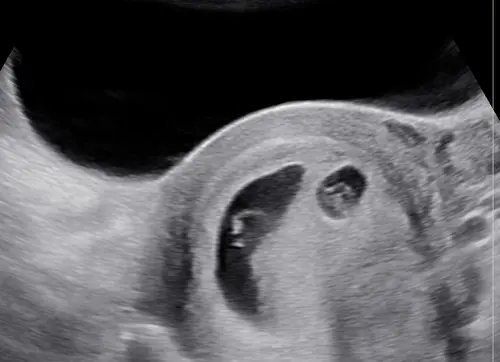

Wij hadden precies hetzelfde. Twee kloppende hartjes gezien met 6 weken, en met 8 weken was er eentje gestopt met groeien. We kregen ook te horen dat er een miskraam zou kunnen volgen en dat dat minder fijn zou kunnen zijn voor de goed groeiende baby. Inmiddels 10+4 en nog geen enkele bloeding gehad. Op de laatste echo met 10+1 deed de baby het fantastisch! Ook konden we nog het vruchtzakje met het vruchtje van ergens in de 6 weken zien zitten. De kans is steeds iets groter dat het blijft zitten :) en hoe groter de baby groeit, hoe minder goed je het andere vruchtje kan zien. Dat verdwijnt dan gewoon omdat het nog zo klein is.